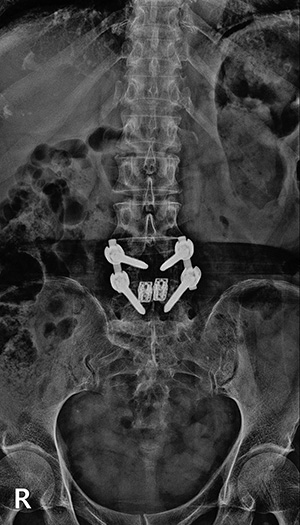

▼ 척추뼈 2개를 묶은 유합술 ▼

유합술 전면 X-ray